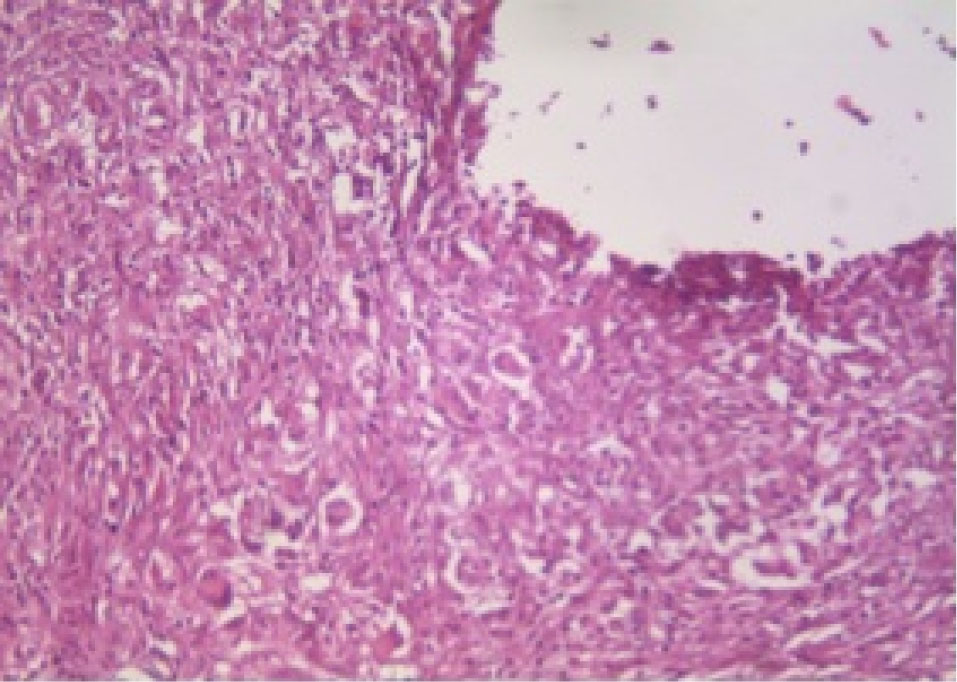

At 30 days after implantation of tubes in the four groups, all of the measured parameters did not show significant difference (P > 0.05). and indicate the histopathological view of granulation tissue at ×40 magnification and giant cells at ×200 magnification.

Figure 2.

Histopathological view of giant cells at ×200 magnification (Resil).